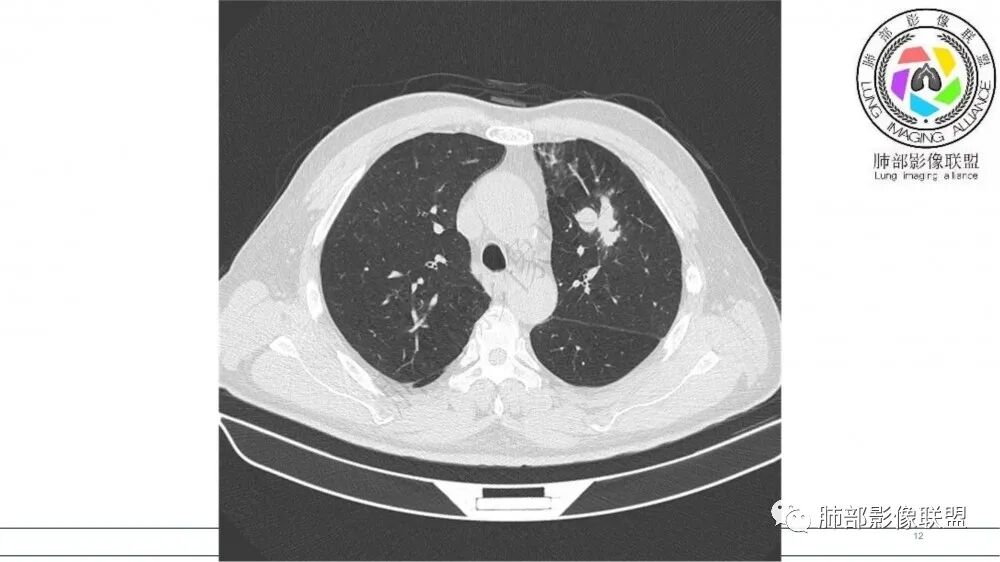

左肺上叶前段支气管内铸形生长软组织影,增强后均匀强化,远侧见斑片状磨玻璃影。考虑恶性病变,粘表?粘液腺?

病灶有强化,粘液栓不考虑。沿着支气管生长,远端小花小草,恶性首先考虑。鉴别结核

老年男性,左肺上叶前段支气管内铸形阴影,增强后病灶不均匀强化,内部有坏死?远端可见斑片状阴影(阻塞性肺炎)。考虑恶性病变,老年人,鳞?类癌?粘表不能排除。

左肺上叶前段支气管杵状指样扩张,内见实性组织阻塞性,并强化明显,边缘饱满,周边多发小斑点影,小花小草征,老年男性,长期吸烟史,方向恶性,首选支气管内浸润鳞Ca可能性大。

男,70岁,吸烟史,咳嗽,胸闷憋气一个月,左肺上叶不规则形软组织密度影,病灶沿支气管走形,周围见粟粒及棉絮样稍高密度影,增强扫描病灶内见少许坏死,考虑鳞癌可能,鉴别结核。

支气管壁病变

左肺上叶前段支气管管壁增厚,腔内软组织填充,有强化,远段阻塞性肺炎,考虑恶性

老年男性,肺气肿,吸烟史,左肺上支气管腔内铸型高密度影,呈指套状,远端多发树芽,增强不均匀强化,考虑鳞癌,鉴别小细胞癌

B3指套征,常规不是鳞癌就是ABPA,有强化丶血管造影征,倾向于鳞癌

老年男性,长期吸烟史。左上肺前段沿支气管走形的指套样病变,增强可见病灶强化(排除结核、ABPA(也无气喘症状)),远端多发点状高密度影。考虑恶性肿瘤,鳞癌可能性大。

指套征明确吧

有强化吧,淋巴结大

恶性

指套征,扩张支气管内软组织强化,远侧肺野阻塞性炎,纵隔、左肺门肿大淋巴结;老年男性,吸烟,考虑鳞癌,鉴别小

指套征:是影像征象,胸部平片表现为手指状密度增高影,以肺门为中心呈放射状分布,CT显示扩张支气管内低密度黏液栓形成或实性病变,呈管状、树枝状或卵圆形密度增高影;支气管扩张伴近端梗阻时,扩张支气管内部黏液分泌物不能排出而形成。可以伴随远端空气潴留征、阻塞性炎症。